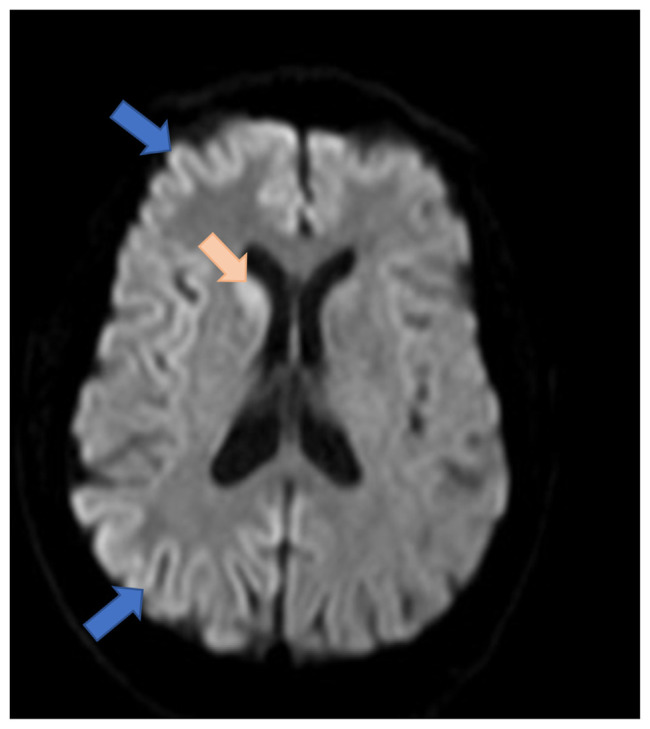

Creutzfeldt-Jakob Disease (CJD) is an exceedingly rare condition with an incidence of one case per million people worldwide. It is diagnosed with symptoms of rapid neurological decline, positive CSF biomarkers, and diagnostic findings on MRI and EEG. There is no known effective therapy for CJD and prompt diagnosis is required to prepare for the expected disease prognosis and goals of care discussions.